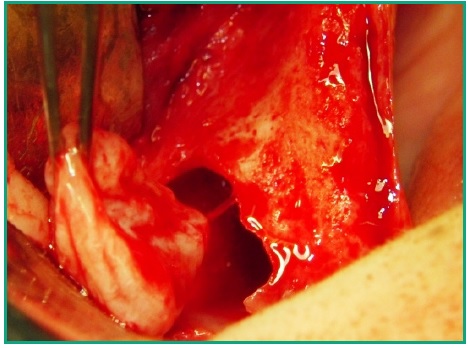

Procedimiento quirúrgico. Mediante la anestesia local correspondiente se procede a realizar una incisión crestal desde la zona tuberosal hasta cerca de la línea media, con una incisión relajante a ese nivel. Previamente a la misma se hizo una punción exploratoria dando como resultado la extracción de un contenido tipo muco purulento. Se elevó un colgajo de espesor total desde adelante hacia atrás, observándose en la zona posterior una fenestración ósea por donde drena abundante contenido mucopurulento (Fig. 6).

Se procede a hacer ostectomía con instrumental rotatorio y abundante irrigación con suero fisiológico, con la finalidad de agrandar la fenestración para facilitar la visibilidad. Con curetas de elevación sinusal se realiza la eliminación total de la lesión mediante la técnica de enucleación y curetaje, procediendo luego a hacer la exéresis del tabique óseo que divide dicha patología (Figs. 7, 8, 9). Por último se realizó un cierre mediante sutura continua con nylon 5 cero (Fig. 10).